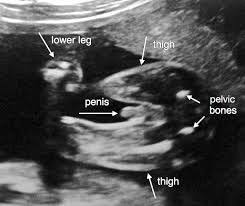

anne karnında 3 aylık bebek cinsiyeti

anne karnında 3 aylık bebek cinsiyeti.

ultrasonla cinsiyet tahmini